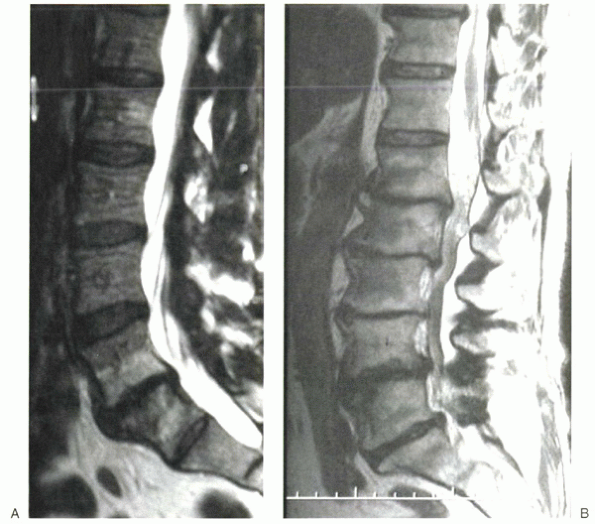

Figure 2-11 T1-weighted (A), T2-weighted (B), and gadolinium-enhanced (C) images of a patient with lumbar osteomyelitis.

|

paraspinal and spinal tissues and the adjacent thecal sac. On

T1-weighted MRI, there is decreased marrow signal in the affected

vertebral bodies, with high signal intensity of the disc on T2 images.

Enhancement is present after intravenous gadolinium administration, and

the enhanced regions are more consistent with an abscess versus a

phlegmon.